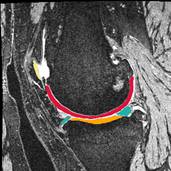

Improving Treatment for Patellar Instability to Reduce Recurrence and Cartilage Degradation

PI: John Elias, PhD

Co-Is: Ceylan Colak, MD; Lutul Farrow, MD; Xiaojuan Li, PhD; Carl Winalski, MD; Mingrui Yang, PhD

Funding Resource: DOD

Abstract:

Lateral patellar instability is a traumatic event that consistently leads to cartilage damage.  Approximately 50% of patients treated for patellar instability develop patellofemoral osteoarthritis (OA) within 25 years, with a higher risk of OA for patients with recurrent instability.  The investigators have initiated this line of research to improve understanding of post-traumatic OA related to patellar instability, identify patients at greatest risk of post-traumatic OA, and optimize treatment methods to reduce the risk of OA. Quantitative MRI, statistical shape modeling and computational models will be used to provide a comprehensive evaluation of the joint structure, tissue composition and functions.

Co-I: Ceylan Colak, MD; Lutul Farrow, MD; Xiaojuan Li, PhD; Carl Winalski, MD; Mingrui Yang, PhD

Sponsors: PAMI Pilot